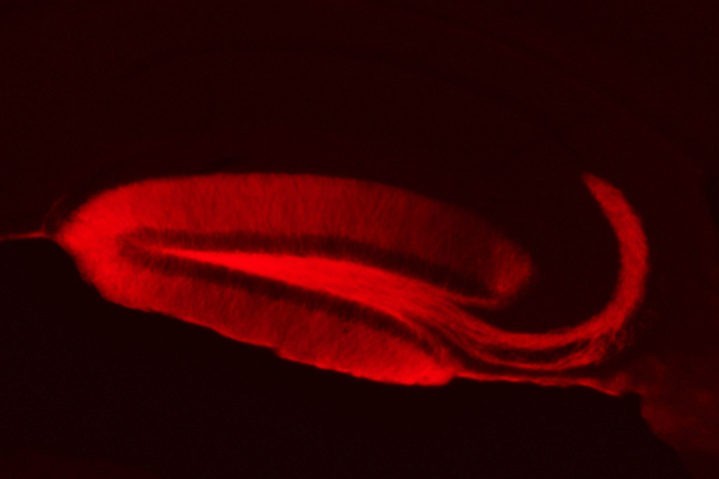

La PS et l’APP sont des protéines abondantes des compartiments présynaptiques, mais leur rôle physiologique y reste un mystère. Partant de l’hypothèse que la PS joue un rôle dans la plasticité présynaptique, les chercheurs ont développé des outils de transfert de gène chez la souris pour combiner la manipulation de gènes « présynaptiques » et la stimulation par une lumière bleue, sélective des synapses mutées (techniques d’optogénétiques combinées à l’électrophysiologie).

Gaël Barthet est un biologiste cellulaire et électrophysiologiste travaillant sur la maladie d’Alzheimer. Depuis 2012, il travaille au sein du groupe de Christophe Mulle à l’Institut Interdisciplinaire des NeuroSciences de Bordeaux où il développe des outils optogénétiques et les associe à l’électrophysiologie, à l’imagerie et à la biochimie pour identifier le rôle de la préséniline et de l’APP dans les mécanismes présynaptiques.